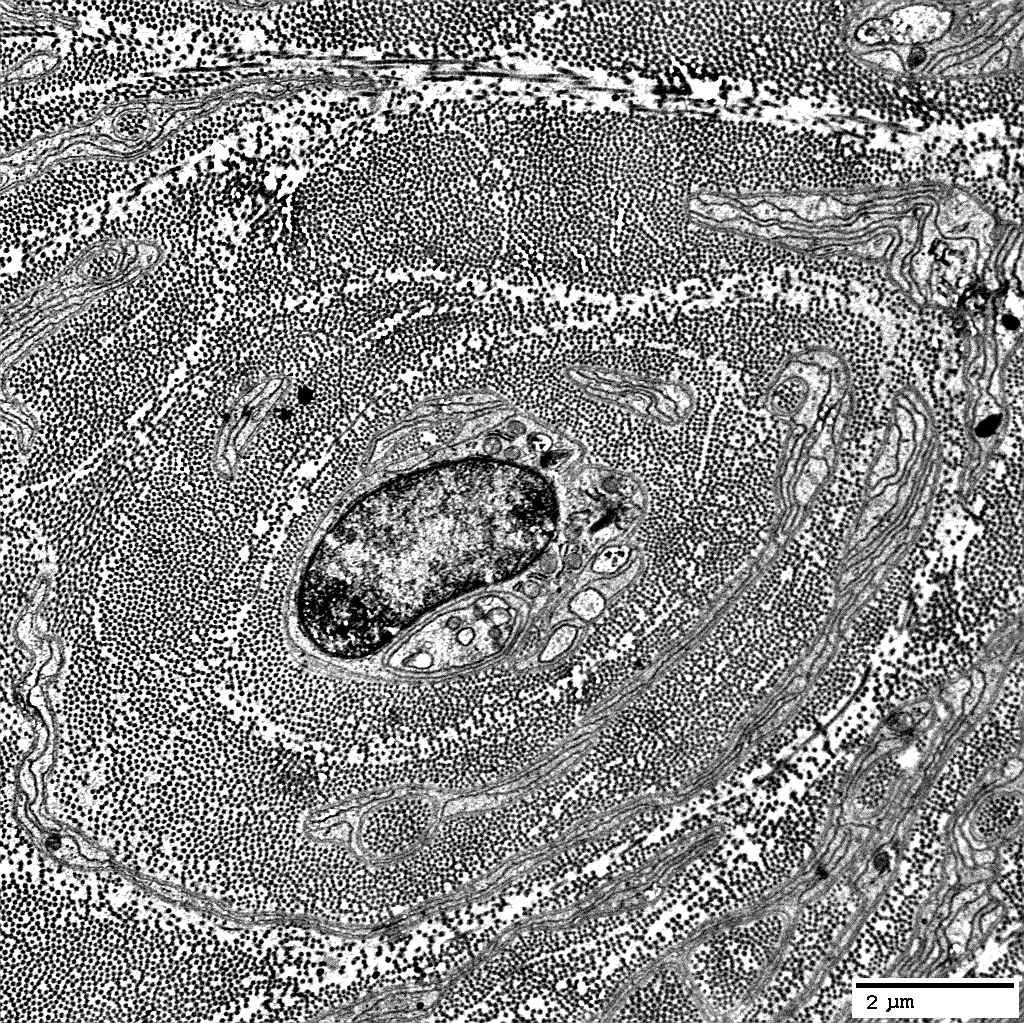

Axons

Reduced numbers: Large & Small

Some onion bulbs have no axons

Some small axons are present in layers within & around onion bulbs